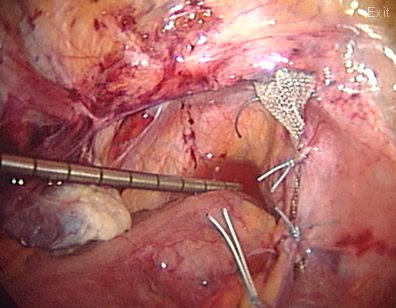

In a different patient with a uterine prolapse, who wants to preserve fertility, a mesh is used to reconstruct the pelvic floor.

The mesh is also attached to the uterosacral ligaments (that normally suspend the uterus to its normal position)

The mesh is attached to the sacrum (tail bone) and buried between the lining of the pelvis and the bones. The uterus is seen back to its normal position in the pelvis.